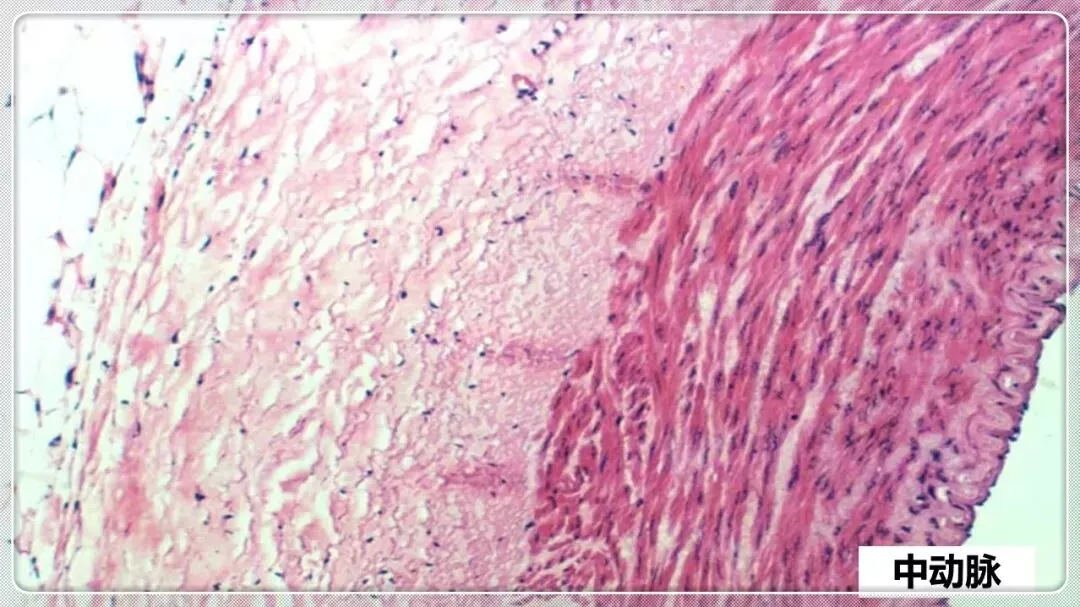

组织学与胚胎学笔记pdf【 常考图谱】

组织学与胚胎学 图谱